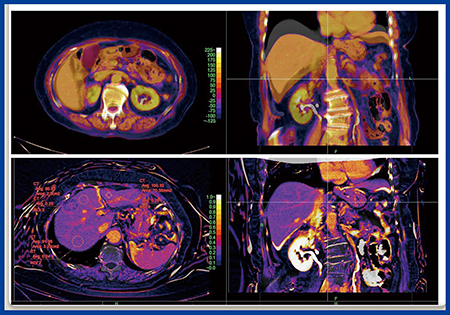

当院における,膵臓がんにおける予後予測因子としてECV解析の方法を図1に示す。基本的には,造影CTの平衡相と単純CTの腫瘍と血管にROIを置き,腫瘍の造影効果から血管の造影効果を除した値をヘマトクリット値で補正する。しかしながら,この手法は煩雑であり,測定誤差が非常に大きいという問題点がある。そこで,Ziostation2の“CT心筋ECV解析”を腹部に応用することを考えた。Ziostation2では造影CTの平衡相から単純CTのサブトラクション時に非剛体位置合わせを行うことで,位置ズレの少ない高精度の差分画像が瞬時に得られる。次に,差分画像上の血管にROIを設定し,ヘマトクリット値を入力するだけでECVマップが簡単に作成できる(図2)。

図2 Ziostation2による腹部のECV解析(W.I.P.)